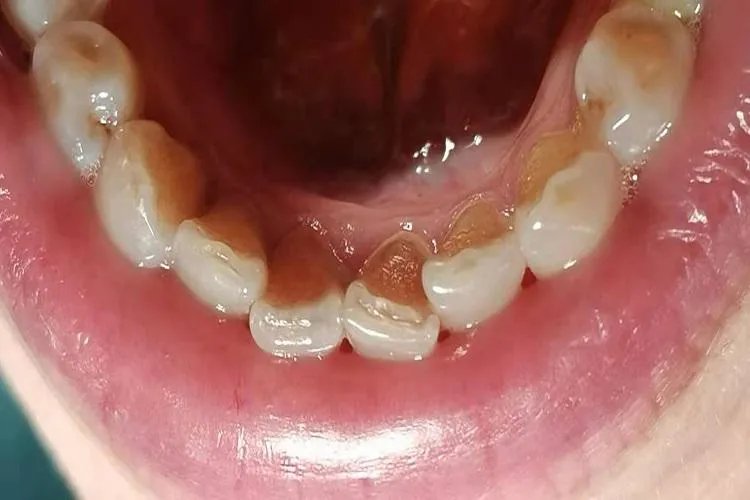

概述牙石是沉积在牙面或修复体上已钙化或正在钙化的菌斑及沉淀物,分为龈上和龈下牙石。龈上牙石呈黄色或白色,体积较大,龈下牙石呈褐色或黑色,较龈上牙石面积大而硬。症状牙石是沉积在牙面或修复体上已钙化或正在钙化的菌斑及沉淀物,由唾液或龈沟液中的矿物盐逐渐沉积而成,分为龈上牙石和龈下牙石。龈上牙石一般沉积在临床牙冠,直接可看到的牙石称为龈上牙石,其呈黄或白色,亦可因吸烟或食物着色而呈深色。一般体积较大,尤其是在与唾液腺导管开口相应处的牙面上沉积更多,如上颌第一磨牙颊面和下颌前牙的舌面。

龈下牙石在龈缘以下的牙面上,肉眼看不到,需深针才能查到的称为龈下牙石,有时在X线片上也可见。龈下牙石呈褐色或黑色,较龈上牙石体积小而硬,一般与牙面的附着比龈上牙石更牢固。龈下牙石见于大多数牙周袋内,通常从釉牙骨质界延伸至袋底附近。